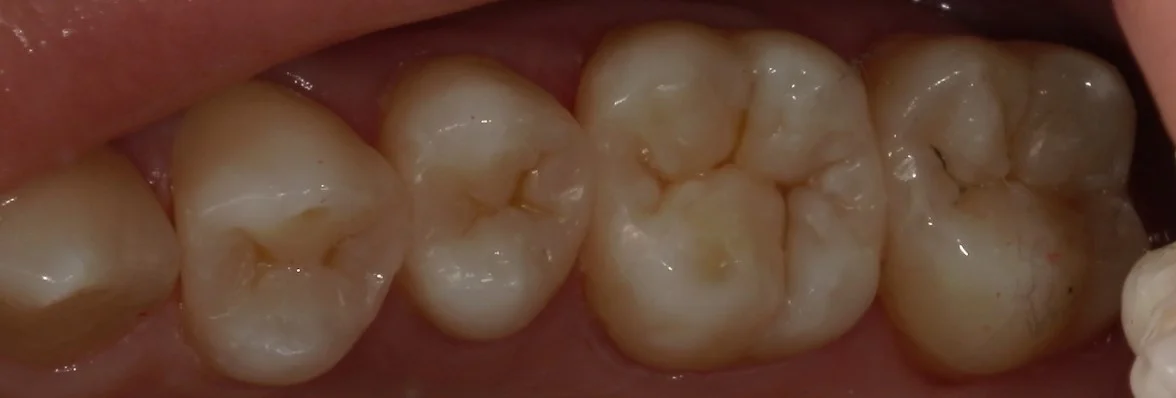

そして詰め終わったのがこちらです。

基本的には噛み合わせの調整は最小になるように行うべきですが、少し多めに調整することになってしまいました。

そして、別アングルからの写真がこちらです。

こちらが、術前。

こちらが術後。

随分と自然な感じに仕上げることが出来たと思います!